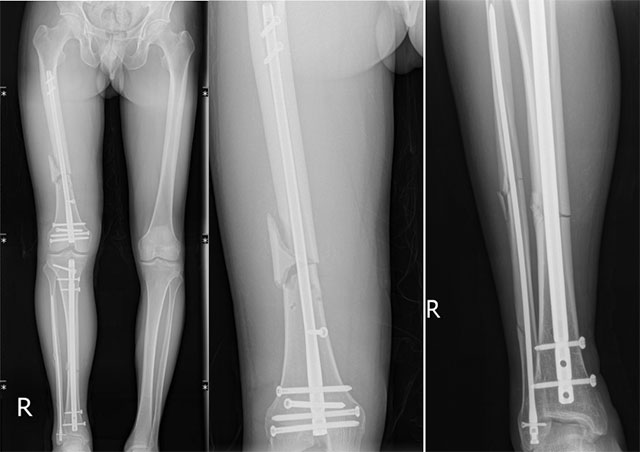

完善X线等相关检查提示:右股骨中下段粉碎性骨折、右胫骨中段骨折、右腓骨中下段多段骨折。通过输血扩容,王先生病情逐渐平稳。

纠正力线,挤压、复位分离骨折块进行闭合复位,通过3个2cm的微创小切口进行股骨逆行髓内钉、胫骨顺行髓内钉、腓骨髓内钉内固定术。

术后X线复查